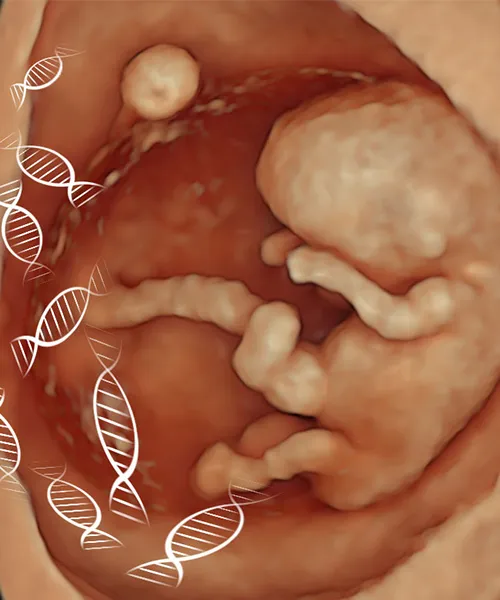

Trichy fetal medicine and fertility centre is a state of art centre for fetal medicine for the past 13 years

It's the first centre in South tamilnadu and second centre in tamilnadu .The team of consultant are fetal medicine specialists with expertise in non invasive and invasive procedures

We are specialised in fetal interventions such as amniocentesis,cvs ,fetal reduction,intra uterine transfusions for rh negative mother's,fetoscopic procedures,RF ablation for twin gestation.we have a multi disciplinary panel for management of abnormal cases with genetic counseling.